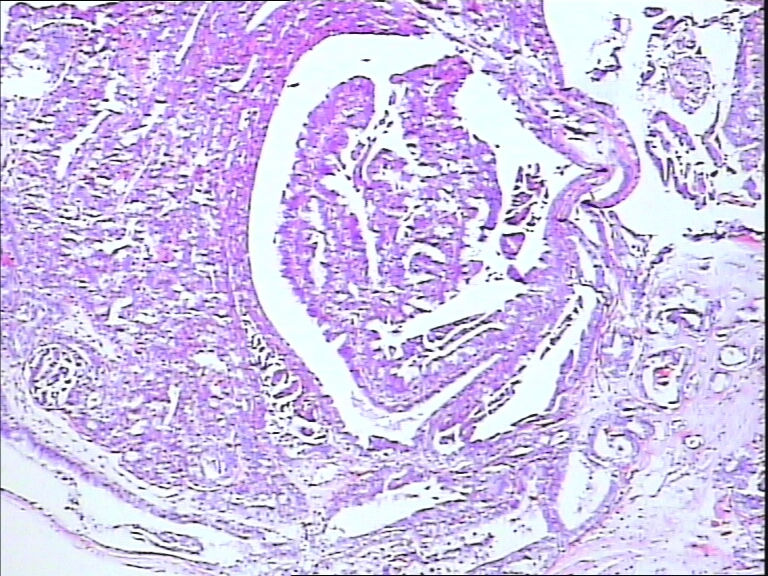

B3785左乳头包块!

42y

左乳头有3mm结节

灰白不整形组织一块:0.7*0.5*0.4

• 左乳头包块!图1

图1

标签:导管内乳头状肿瘤

诊断导管内乳头状瘤.做免疫组化肌上皮标记,排除癌变

导管内乳头状瘤

导管内乳头状瘤,导管上皮不典型增生。

乳头腺瘤(nipple duct adenoma)或称乳头的乳头状瘤

导管内乳头状瘤,局灶伴不典型增生。

导管内乳头状肿瘤.做免疫组化肌上皮标记,排除癌变。

有异性,考虑导管内乳头状癌

导管内乳头状结构,细胞无异型性,诊断导管内乳头状瘤。